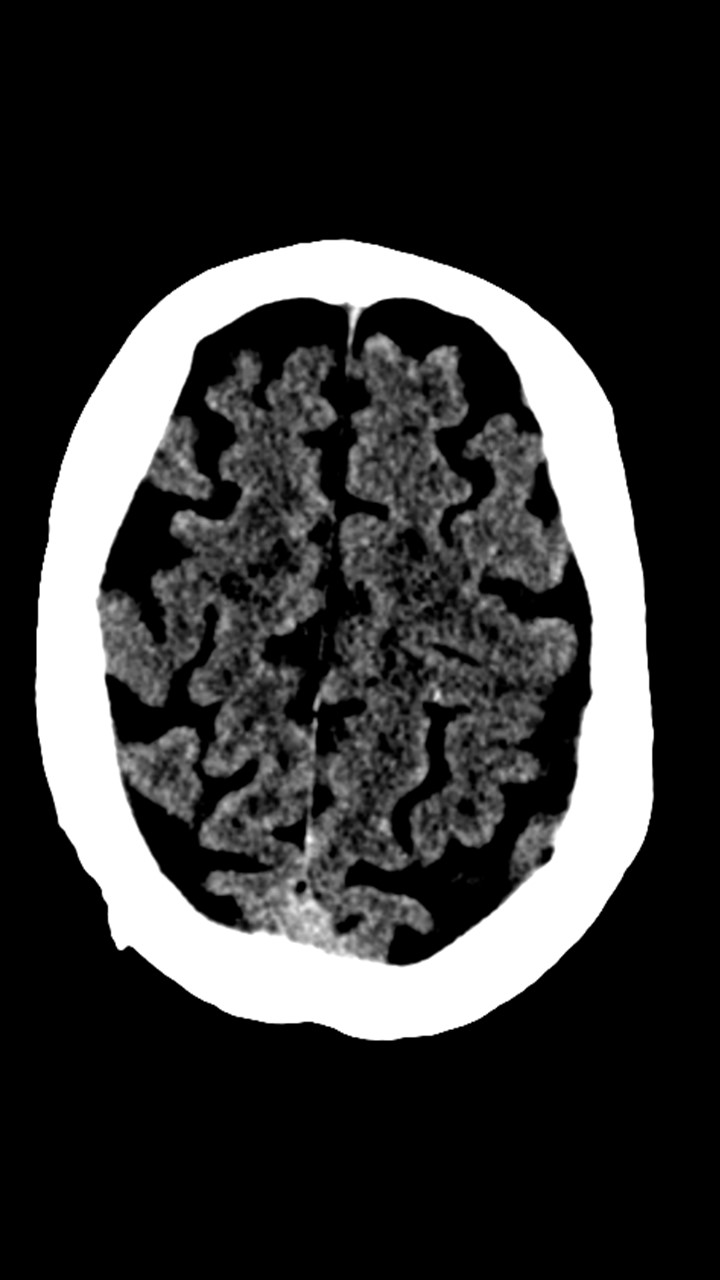

Hallazgos de TC de craneo:

• Cambios de leucoaraiosis periventricular.

• Hay zonas de hipodensidad subcortical fronto-parietal superior predominantemente izquierdas, de aspecto inespecíficos.

• Los halazgos son inespecificos, ante la ausencia de patología hemorragica aguda se decide continuar con el protocolo habitual.